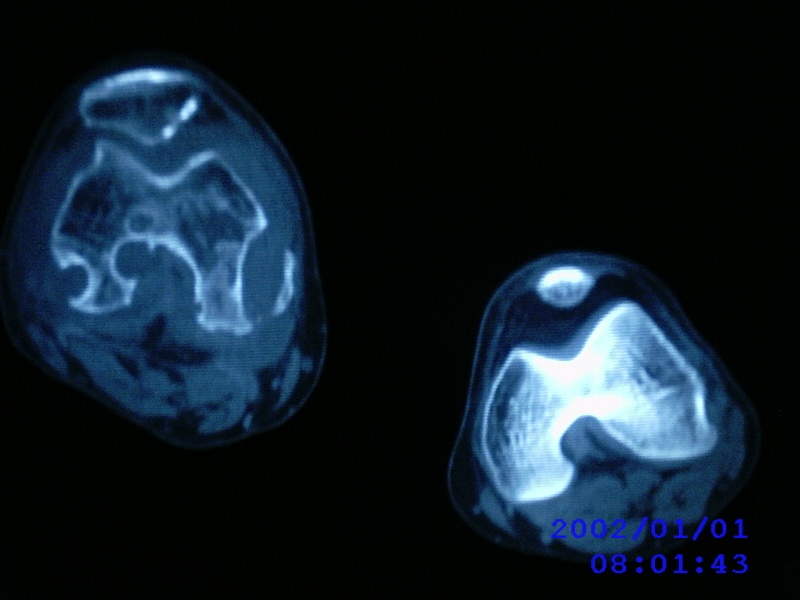

患者,男性,57岁,右侧膝关节疼痛伴肿脹10余年,加重一个月。

关节积液,关节间隙变窄,边缘骨破坏。考虑膝关节tb

关节积液,关节间隙变窄,骨质疏松,多发骨破坏,边缘轻度硬化,近端胫腓骨髓腔软组织充填,患者病史较长,支持考虑结核

有皮质的破坏~有死骨存在

结合临床表现,考虑结核。。。。课医照个胸片

多发骨破坏,骨质疏松,关节积液。考虑右膝关节结核。